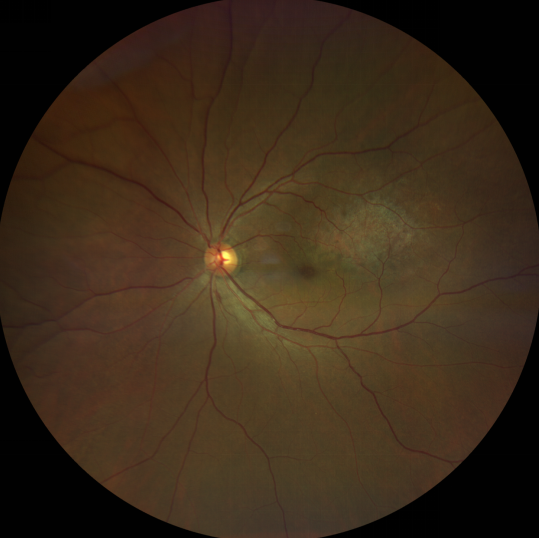

脈絡(luò)膜黑色素瘤是成年人常見的眼內(nèi)惡性腫瘤,其患病率在我國居眼內(nèi)惡性腫瘤的第二位,僅次于視網(wǎng)膜母細(xì)胞瘤。其惡性程度高,不僅可致患者喪失視力,而且嚴(yán)重威脅患者生命,即使在沒有明確轉(zhuǎn)移前摘除患眼眼球,其5年死亡率也有17%-53%。

脈絡(luò)膜黑色素瘤是葡萄膜惡性腫瘤中較多的一種。葡萄膜腫瘤主要發(fā)生于脈絡(luò)膜、睫狀體和虹膜。其中,脈絡(luò)膜腫瘤占80%,睫狀體腫瘤占12%,虹膜腫瘤占8%。惡性程度高的腫瘤主要發(fā)生于脈絡(luò)膜。發(fā)生于睫狀體的腫瘤惡性程度偏低,發(fā)生于虹膜的腫瘤多數(shù)為良性。脈絡(luò)膜黑色素瘤的特點是惡性程度高、易侵襲轉(zhuǎn)移、預(yù)后極差,嚴(yán)重威脅患者的視力和生命。其發(fā)病率有種族差異性,以高加索及白種人居多,黑人發(fā)病率低,亞洲人居于中間。

脈絡(luò)膜黑色素瘤患者在發(fā)病早期無眼痛等癥狀,當(dāng)腫瘤較小時較難發(fā)現(xiàn),隨著病程進(jìn)展,腫瘤增大,發(fā)生滲出性視網(wǎng)膜脫離或累及黃斑,視力下降才就診。

脈絡(luò)膜黑色素瘤惡性程度高,50%的患者會發(fā)生轉(zhuǎn)移,轉(zhuǎn)移到肝、肺等遠(yuǎn)處臟器,常見的轉(zhuǎn)移方式是經(jīng)鞏膜導(dǎo)管擴散,經(jīng)視神經(jīng)蔓延者罕見。一旦發(fā)生轉(zhuǎn)移,1年生存率只有10%,即絕大多數(shù)病人在半年至1年間會失去生命。因此,早期診斷和選擇合適的治療方式對有效提高局部腫瘤的控制率、降低腫瘤的遠(yuǎn)處轉(zhuǎn)移率、延長患者的生存率具有重要意義。